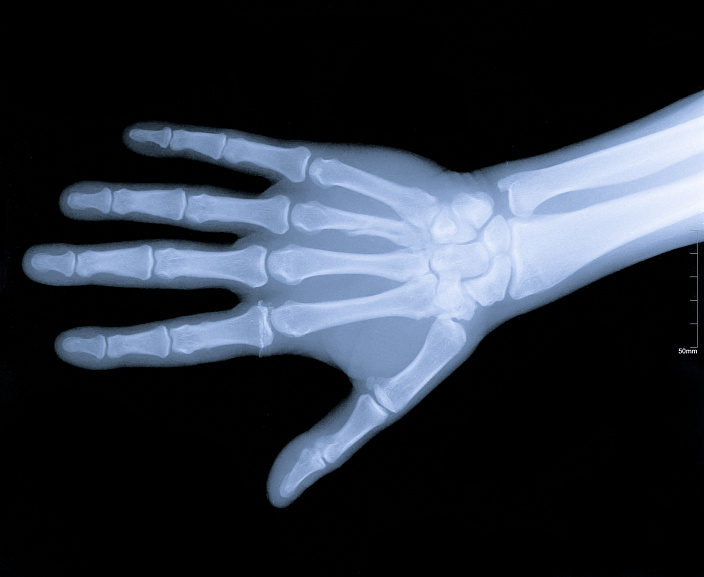

Анатомия кисти руки человека довольно сложна. Поскольку это очень подвижная часть тела, в ней множество костей и суставов, связок и мышц, также человеческие пальцы, в отличие от конечностей животных, имеют ногти. Кожа рук также отличается от кожного покрова тела, имея специфические складки и особую чувствительность. Итак, начнём с обзора костей. Кости кисти делятся на три отдела: запястье, включающее восемь костей; пясть, состоящая из пяти длинных костей, и пальцы, насчитывающие в общей сумме четырнадцать фаланг. Фаланги относятся к трубчатым костям, в отличие от остальных костей, составляющих кисть. Все кости довольно мелкие и расположены друг к другу очень близко.

Благодаря тому, что костей много и они небольшие, кисть имеет такую пластичность и подвижность, однако из-за этого при травмах работоспособность кисти заметно снижается. Кости запястья образуют как малоподвижные соединения (например, в области запястья), так и суставы. Лучезапястное соединение имеет форму полукруга и обеспечивает сгибание и разгибание кисти. Это очень сложный сустав, дающий кисти широкий диапазон движений. Кости запястья соединены между собой связками и образуют прочное сочленение, способное выдерживать большие нагрузки при опоре на кисть. У основания большого пальца расположен седловидный сустав, позволяющий совершать движения в двух осях, что делает большой палец очень функциональным.

Кости фаланг имеют шаровидные соединения, что позволяет пальцам сгибаться только в одной плоскости. Из-за этого пальцы весьма подвержены травмам. В отличие от остальных пальцев, насчитывающих по три фаланги, большой палец короче и состоит всего из двух костей. Кисть имеет широкую сеть инервации, отвечающую за осязание, движение, работу сальных и потовых желёз и терморегуляцию. Вообще руки тесно связаны с психическим состоянием человека. В моменты стресса руки часто трясутся, немеют, из них всё валится, человек утрачивает способность владеть ими в полной мере. Также при эмоциональных всплесках ладони могут похолодеть или вспотеть.